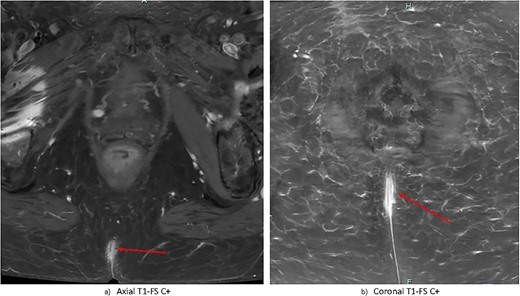

Contrast-enhanced magnetic resonance imaging (MRI) of the pelvis demonstrated nonspecific, irregular enhancement in the natal cleft measuring 6 × 13 × 28 mm, with no other visible mass lesion (Fig. 2). There was no visible invasion of underlying structures. There was no notable sinus tract demonstrated; however there was a small subcutaneous cystic focus noted 5 mm to the left of the superior margin of the natal cleft. There were no bony or regional nodal metastases. Full report in Appendix B.

Gadolinium-contrast enhanced MRI images at time of diagnosis showing small-volume, superficial disease in (a) axial and (b) coronal planes. There is evidence of nonspecific superficial skin enhancement (arrows) but no evidence of significantly infiltrative disease or nodal metastases.